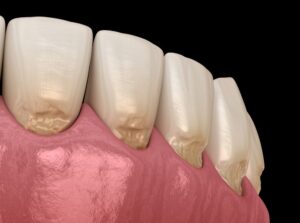

くさび状欠損

くさび状欠損は、虫歯に次いで多く見られる歯の硬組織疾患で、特に上の奥歯の歯と歯ぐきの境目付近に発生します。

エナメル質や象牙質が部分的に欠け、断面がくさびのような三角形の形状になることから、この名前がついています。

原因は主に二つあり、一つは強い咬合力、もう一つは不適切なブラッシングです。

歯ぎしりや食いしばりを繰り返すことで、微細なひびが生じて欠損が進行します。

また、硬い毛の歯ブラシで強く磨く習慣があると、長期間の摩擦によって歯が削られていくこともあります。

くさび状欠損は知覚過敏と併発することが多く、「冷たい水がしみる」という症状で初めて気づく方も少なくありません。